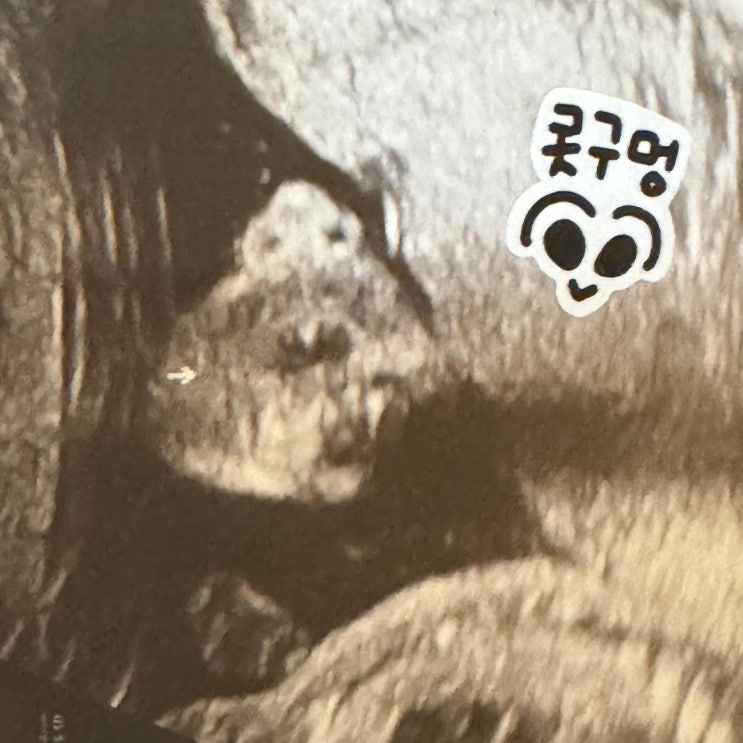

[임신 일기] 증상의 연속에 연속 - 19주부터 22주의 기록 (+정밀 초음파, 안면 홍조, 좌골 신경통)

확실한 태동을 느끼며 보낸 지난 한 달 엄마 나 여기 있어요? 하고 잊을 틈 없이 차주니까 혼자가 아닌 ...